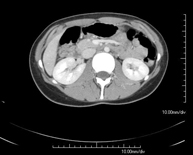

- TC Abdominopélvico

Prueba diagnóstica que consiste en obtener imágenes bi y tridimensionales del abdomen y de la pelvis de alta definición anatómica (estructuras óseas, estructuras vasculares, hígado, páncreas, vesícula biliar, riñones, glándulas suprarrenales, bazo, intestino delgado y grueso, vejiga, útero y ovarios, próstata y vesículas seminales, uréteres, etc.) mediante el empleo de un equipo de TC (Tomografía Computarizada). La mayoría de estudios requieren el empleo de contraste yodado.